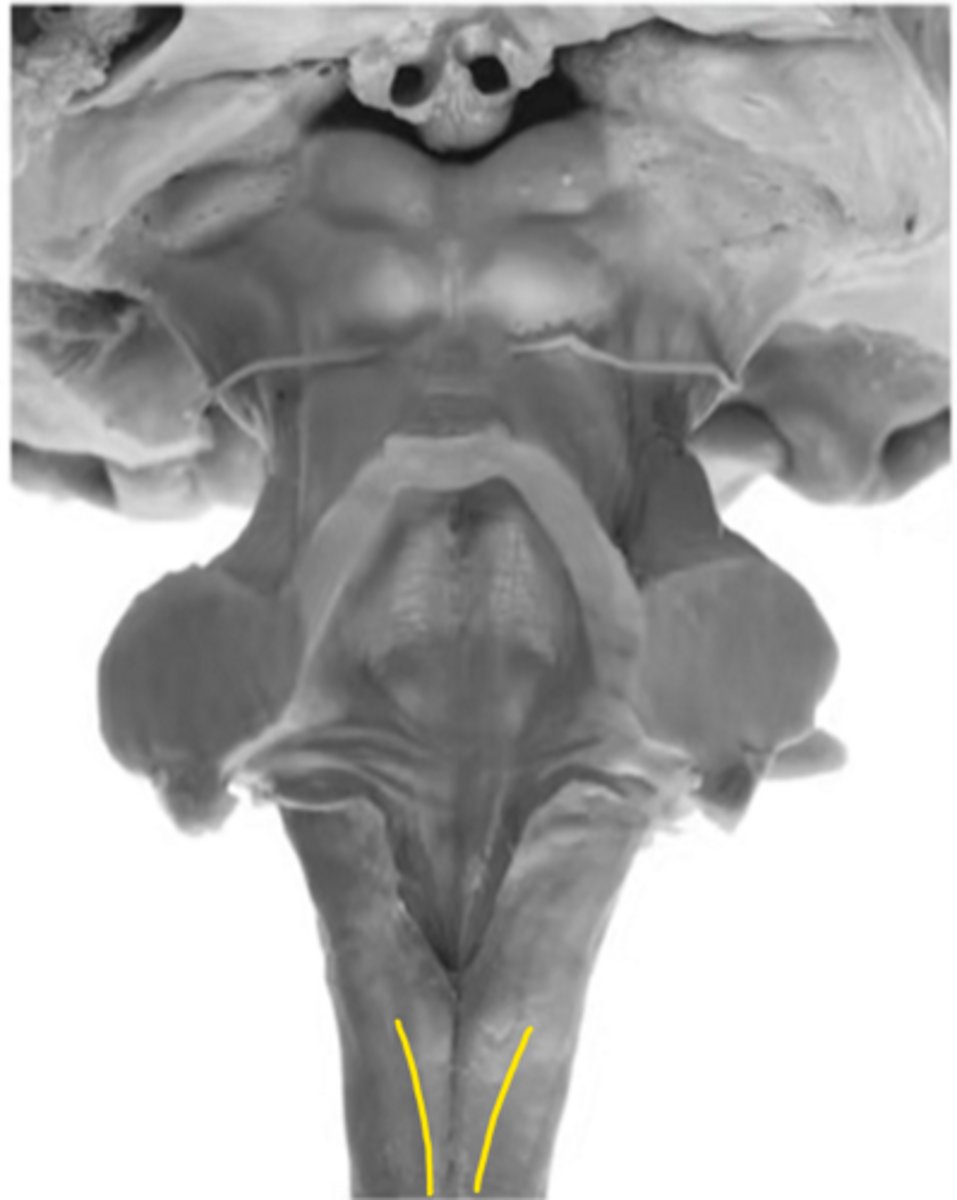

motor decussation

ID the structure

central gray

central canal

closed medulla

ID the brainstem level